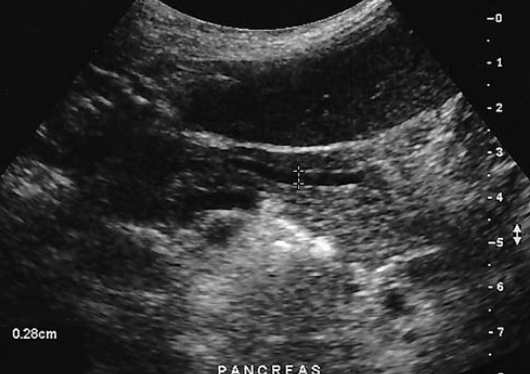

a patient presents with a history of elevated liver function tests. An anechoic tubular structure is identified in the body of the pancreas. This structure most likely represents the

pancreatic duct